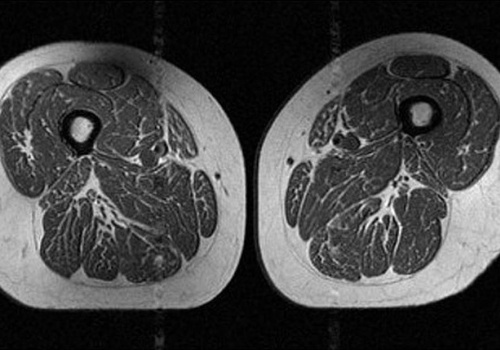

Najnowsze badania naukowców, opublikowane w czasopiśmie Radiology i prezentowane przez Radiological Society of North America (RSNA), pokazują niepokojące zjawisko. Dieta bogata w żywność wysoko przetworzoną powoduje okładanie się tłuszczu nie tylko pod skórą, ale również wewnątrz mięśni.